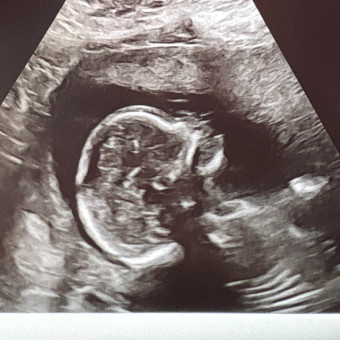

Jennings can’t wait to meet everyone! He’s already loved so much.